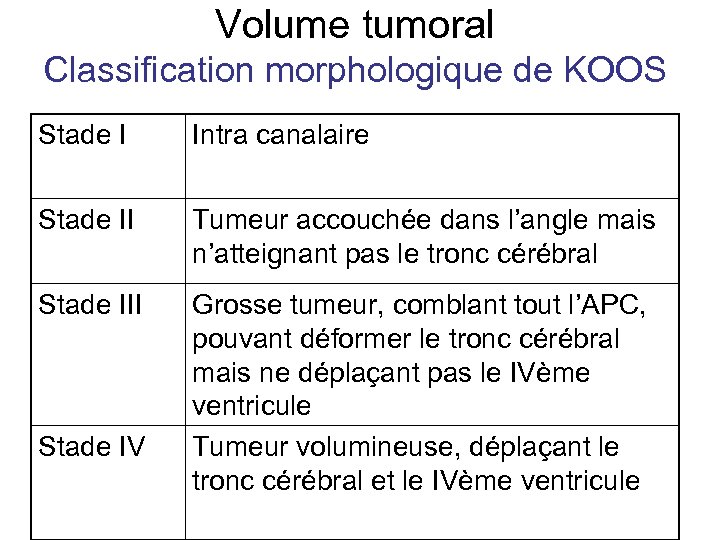

Volume tumoral Classification morphologique de KOOS Stade I Intra canalaire Stade II Tumeur accouchée dans l’angle mais n’atteignant pas le tronc cérébral Stade III Grosse tumeur, comblant tout l’APC, pouvant déformer le tronc cérébral mais ne déplaçant pas le IVème ventricule Tumeur volumineuse, déplaçant le tronc cérébral et le IVème ventricule Stade IV

Volume tumoral Classification morphologique de KOOS Stade I Intra canalaire Stade II Tumeur accouchée dans l’angle mais n’atteignant pas le tronc cérébral Stade III Grosse tumeur, comblant tout l’APC, pouvant déformer le tronc cérébral mais ne déplaçant pas le IVème ventricule Tumeur volumineuse, déplaçant le tronc cérébral et le IVème ventricule Stade IV

Indications en fonction du volume • Stade III et IV : traitement chirurgical en fonction des contre indications • Stade I à discuter en fonction de l’état de la fonction auditive et état général: – Surveillance – Intervention chirurgicale – Radiothérapie stéréotaxique • Stade II à discuter en fonction de l’état de la fonction auditive et état général – Intervention chirurgicale – Radiothérapie stéréotaxique

Indications en fonction du volume • Stade III et IV : traitement chirurgical en fonction des contre indications • Stade I à discuter en fonction de l’état de la fonction auditive et état général: – Surveillance – Intervention chirurgicale – Radiothérapie stéréotaxique • Stade II à discuter en fonction de l’état de la fonction auditive et état général – Intervention chirurgicale – Radiothérapie stéréotaxique